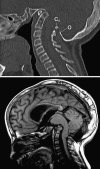

Background: The embryology of the bony craniovertebral junction (CVJ) is reviewed with the purpose of explaining the genesis and unusual configurations of the numerous congenital malformations in this region. Functionally, the bony CVJ can be divided into a central pillar consisting of the basiocciput and dental pivot and a two-tiered ring revolving round the central pivot, comprising the foramen magnum rim and occipital condyles above and the atlantal ring below. Embryologically, the central pillar and the surrounding rings descend from different primordia, and accordingly, developmental anomalies at the CVJ can also be segregated into those affecting the central pillar and those affecting the surrounding rings, respectively.